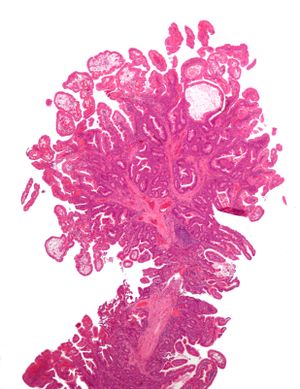

السليلة أو الپوليپ polyp، هو نمو غير طبيعي لأنسجة البارزة من الأغشية المخاطية. لو كانت معلقة بالسطح بواسطة عنيقة مستطيلة ضيقة، يقال أنها معنقة. ولو لم يكن هناك عنيقة، يقال أنها لاطئة. عادة ما تجد السلائل في القولون، المعدة، الانف، الجيوب الأنفية، المثانة والرحم. توجد أيضاً في أماكن أخرى بالجسم يحتوي على أغشية مخاطية مثل عنق الرحم،[1] الأحبال الصوتية، والأمعاء الدقيقة.

Tubular Adenoma (Villous, Tubulovillous) | Tubular glands with elongated nuclei (at least low-grade atypia) | نعم | ||

- البوليبات الورمية: سليمة لكن قابلة للتسرطن, لها ثلاثة نماذج: أورام غدية انبوبية نسبتها 75% وأورام غدية زغابية نسبتها 10% وأورام غدية أنبوبية زغابية نسبتها 15%.

السلائل الغدية